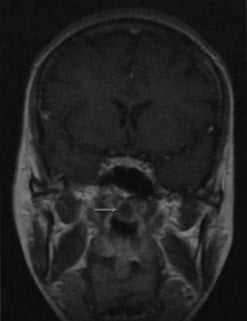

МРТ без контрастного усиления. На Т2-взвешенном изображении визуализируется киста Торнвальдта, расположенная по передней срединной линии в крыше носоглотки между брюшками длинной мышцы шеи. Содержимое кисты обычно гиперинтенсивно на Т2-взвешенном изображении.

Т1 -взвешенное изображение после введения гадолиния. Здесь содержимое кисты выглядит изо- или гипоинтенсивно по отношению к мышце. Гиперинтенсивное кольцо вокруг кисты представляет собой стенку кисты и усиленную слизистую оболочку глотки после введения гадолиния (стрелка)